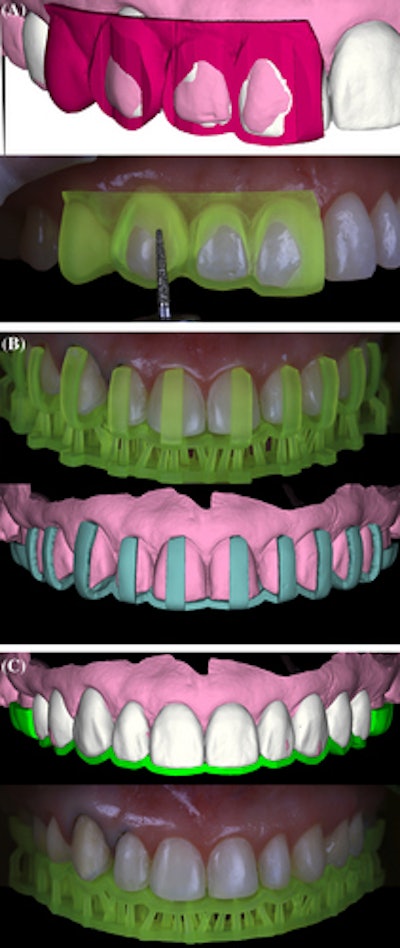

First, a smile frame with ideal dental proportions was drawn on photos and overlapped with intraoral scans. The desired smile was then simulated digitally to provide an overview of treatment possibilities.

Using a digital library containing different shapes and sizes of natural teeth, a digital wax-up was designed based on the patient's proportions. This technique made it possible to replicate anatomical details and the surface texture of natural teeth in the wax-up. To analyze the relationship between the patient's smile and facial expressions, the digital wax-up was placed over the photos, they wrote.

After a two-month healing period, photos and an intraoral scan were taken to analyze the patient's periodontal condition and begin restorative treatment. Based on the previous digital wax-up, shells were printed and tried on.

Restoration began by manufacturing resin guides to orient teeth preparation. The initial digital wax-up was used as a reference, and preparation guides were designed and printed, according to the report.

Clinicians performed tooth reduction according to the first preparation guide. Using additional guides, labial and incisal reduction were performed. The monolithic CAD/CAM restorations, which were designed and milled using a lithium disilicate material, provided a natural appearance.